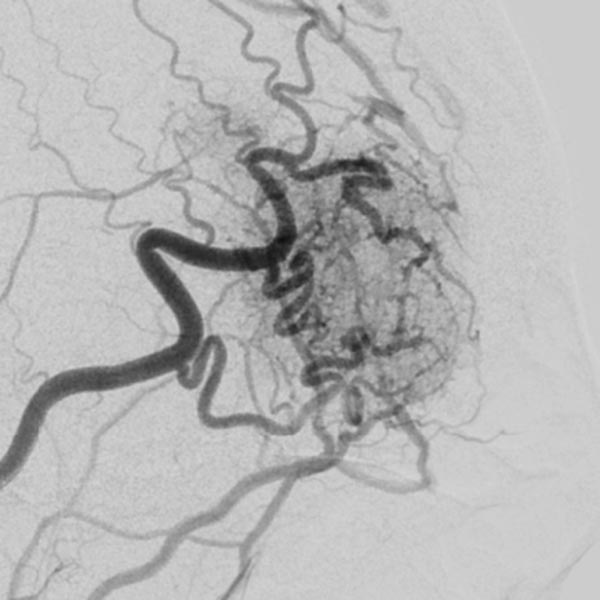

Die digitale Subtraktionsangiographie (DSA) über rechte die Arteria carotis externa und die Arteria temporalis superficialis zeigt eine feinfistulöse AVM mit deutlich dilatierten Feederarterien an der rechten Stirn und sofortigem venösen Abstrom.

Der Mikrokatheter wurde bis direkt zum Nidus vorgebracht. Nach Darstellung des Nidus sofortiger, direkter venöser Abstrom (DSA, venöse Phase) aus der Läsion über dilatierte Venen. Dies sichert die Diagnose einer AVM.

DSA-Bild mit Darstellung des gesamten arteriellen Einstroms, des Nidus und des venösen Abstroms der AVM vor der Embolisation. Die Angioanatomie der hier noch unbehandelten AVM ist klar erkennbar.